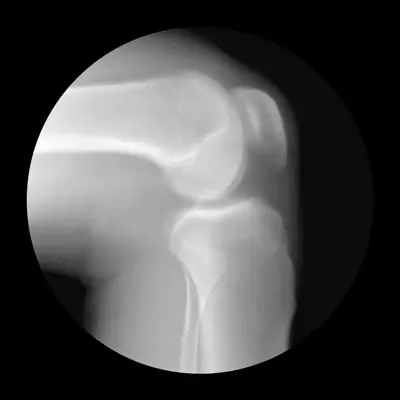

Рентгенологическое исследование при движении позволяет врачам контролировать корректность выполненной репозиции вывиха.

Помимо физического осмотра, необходимо провести инструментальные исследования. Во многих случаях достаточно рентгенографического обследования, которое помогает врачу определить тип и степень вывиха, а Выявить переломы и повреждения костей.